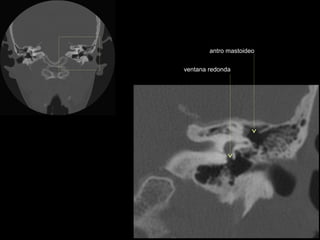

antro mastoideo

ventana redonda